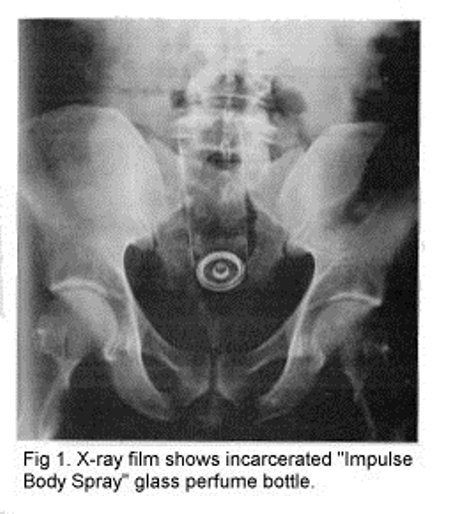

2. Een flesje Parfum

Wederom een advocaat die wel vaker een flesje parfum in z’n anus had geduwd. Dit keer kreeg hij het flesje er echter niet meer uit en moest hij naar het ziekenhuis om het te laten verwijderen. Zijn kont zal in ieder geval een tijdje lekker geroken hebben.